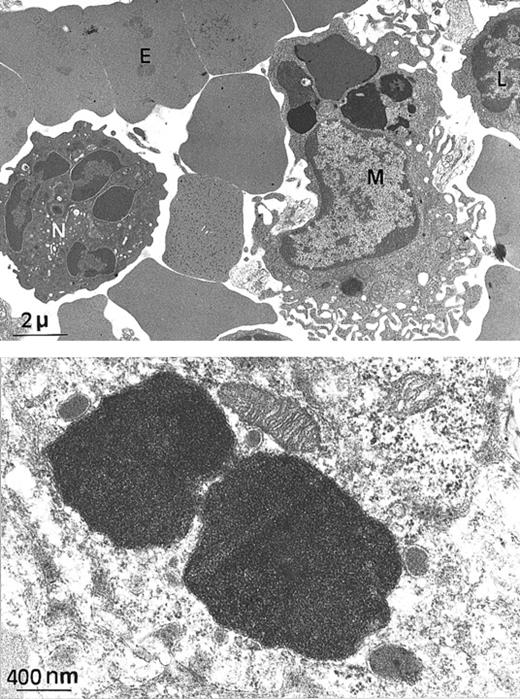

Since H ferritin has been shown to control the size of the labile iron pool (LIP) and to affect the IRE-IRP interactions, we explored the possibility that the Fth+/− mice, although apparently normal, might have unbalanced iron homeostasis. We intercrossed Fth+/− mice and analyzed heterozygous Fth knockout mice and their control littermates at several ages up to 45 weeks of age. These mice were of mixed C57Bl/6 × 129SV genetic background. We performed Perls staining on various tissues and quantitative measurements of tissue iron by atomic absorption spectroscopy. The amount of iron that accumulated in the liver, spleen, and heart of bothFth+/+ and Fth+/− mice increased with age during the first 3 or 4 months of postnatal development but did not noticeably differ between controls and heterozygous mice (Table 1). However, there was important variability in tissue iron among individual mice of the same age and same genotype. This might be due to C57BL/6 and 129SV iron-related genes segregating in the F2 mice. It is noteworthy that in mice, the spleen appears as a major site of iron storage since iron accumulation is readily detectable by Perls blue staining (Figure 1C, E-F), whereas it is not in the liver (Figure 1A). Ultrastructural analysis of a 25-week-old spleen shows that iron accumulates only in macrophages (Figure2A). Higher magnification of the electron-dense particles shows the typical microcrystalline array of iron deposits, surrounded by membranes (Figure 2B). There was no visible cell damage in these iron-loaded macrophages in either genotype (not shown). We also assessed the ability of the knockout mice to face an iron challenge by 3 subcutaneous injections of iron dextran over a 2-week period (30 mg total iron) into 45-week-old mice. Surprisingly, this induced massive iron loading of the liver, whereas iron deposits did not change much in the spleens (Table 1). Both genotypes developed similar iron overload. These results highlight some unusual features of iron homeostasis in mice, especially a progressive accumulation of iron in spleen macrophages, which is not modified by reduced H ferritin content.

Electron microscopy of spleen from a

Fth+/− mouse. (A) At this low magnification, several spleen cells are visible, such as macrophage (M), lymphocyte (L), neutrophil (N), and erythrocyte (E). Arrows indicate electron-dense intracytoplasmic vesicles likely to contain iron (× 4000). (B) Higher magnification of 2 macrophage intracytoplasmic vesicles, showing typical paracrystalline arrangements of iron deposits (no counterstaining, × 20 000).

Tissue iron stores in mice progressively increase in the post-natal period up to 25 weeks of age. Surprisingly, in adult mice, the spleen appears as the major site of iron storage and contains 4- to 5-fold more iron than the liver. This spleen iron is probably partially associated with hemosiderin, since the iron–to–L ferritin ratio is different in spleen and liver, being 37μg iron to 47μg L ferritin in the liver vs 205 μg iron to 144μg L ferritin in the spleen. Electron micrograph studies revealed that this iron is present almost exclusively in macrophages and is located within vesicular structures. Microcrystalline arrays of iron deposits are seen in lysosomelike structures and have the typical appearance of iron deposits seen in the liver of hemochromatotic patients.21 This iron accumulation in the spleen is probably strain-specific and could be related to the presence of a different allele at a locus that governs iron recycling following red blood cell destruction in macrophages. Abnormal iron loading of the spleen has been observed in ceruloplasmin knockout mice. In that case, the targeting was obtained in Swiss-Webster mice, which do not accumulate iron in their spleens, and spleen iron overload developed only following absence of ceruloplasmin expression.22 It is possible that various levels of ceruloplasmin expression in the different strains is responsible for incomplete iron recycling from macrophages. However, subunit composition of the ferritin molecule is not a major regulator of this process, since spleen iron levels were very similar inFth+/+ and Fth+/− mice. This retention of iron in the spleen is probably independent of the rate of intestinal iron absorption. Increased iron absorption in the gut of HFE knockout mice results in liver iron overload and diminished spleen iron content.23 Furthermore, the high accumulation of iron in the spleen is wiped out by inactivation of the heme oxygenase 1 gene, which is the major actor of macrophage heme degradation and iron recycling, suggesting that spleen iron accumulates following destruction of red cell heme in macrophages.24